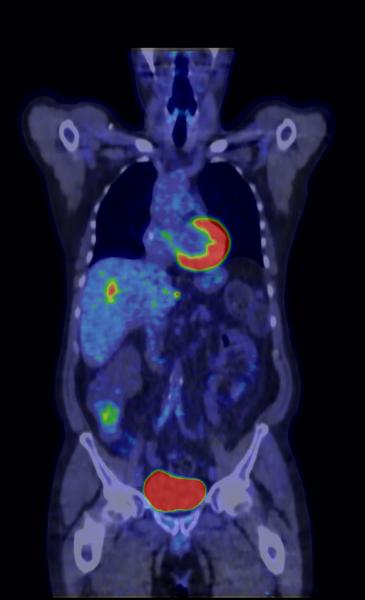

Information hidden in imaging tests could help doctors more accurately choose the radiation therapy dose needed to kill tumors, suggests a study of more than 300 cancer patients presented at the 56th Annual Meeting of the American Association of Physicists in Medicine (AAPM).